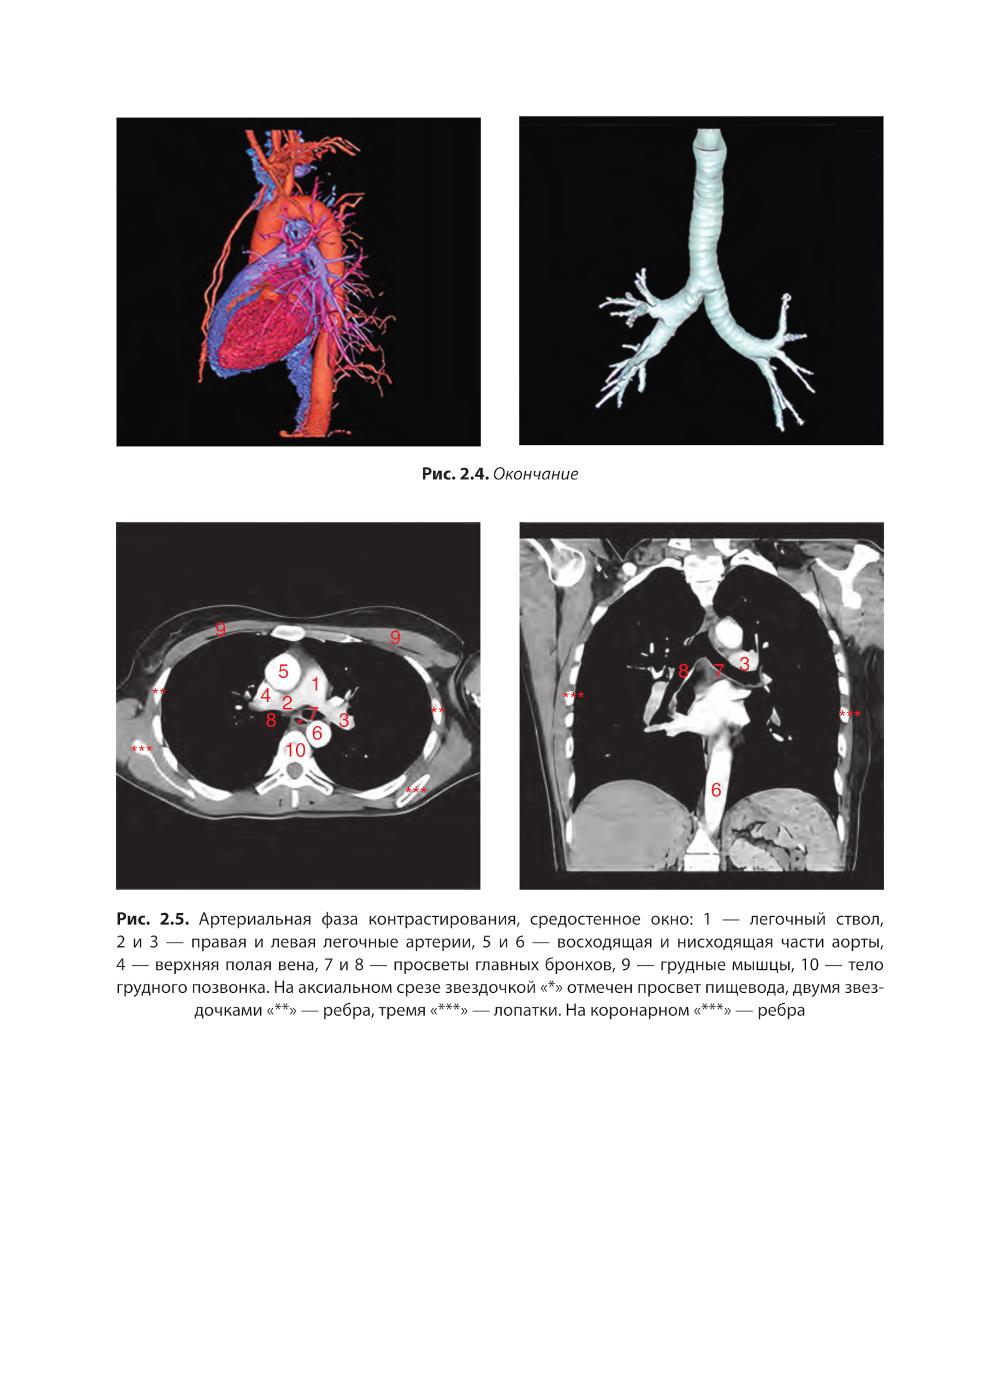

Практическое руководство представляет собой современное пособие, предназначенное для врачей-рентгенологов, пульмонологов, педиатров, терапевтов и других специалистов, занимающихся диагностикой и лечением заболеваний органов грудной клетки. В нем подробно рассмотрены методы лучевой диагностики, включая рентгенографию, компьютерную томографию (КТ). Приведены актуальные рекомендации по интерпретации лучевых изображений, основанные на последних достижениях медицинской науки и клинических рекомендациях. Руководство богато иллюстрировано высококачественными рентгенограммами, КТ-снимками, что делает его незаменимым инструментом для обучения и повышения квалификации специалистов. Издание адресовано как опытным врачам, так и студентам медицинских вузов, ординаторам и аспирантам, изучающим лучевую диагностику.| Издательство | ГЭОТАР-Медиа |